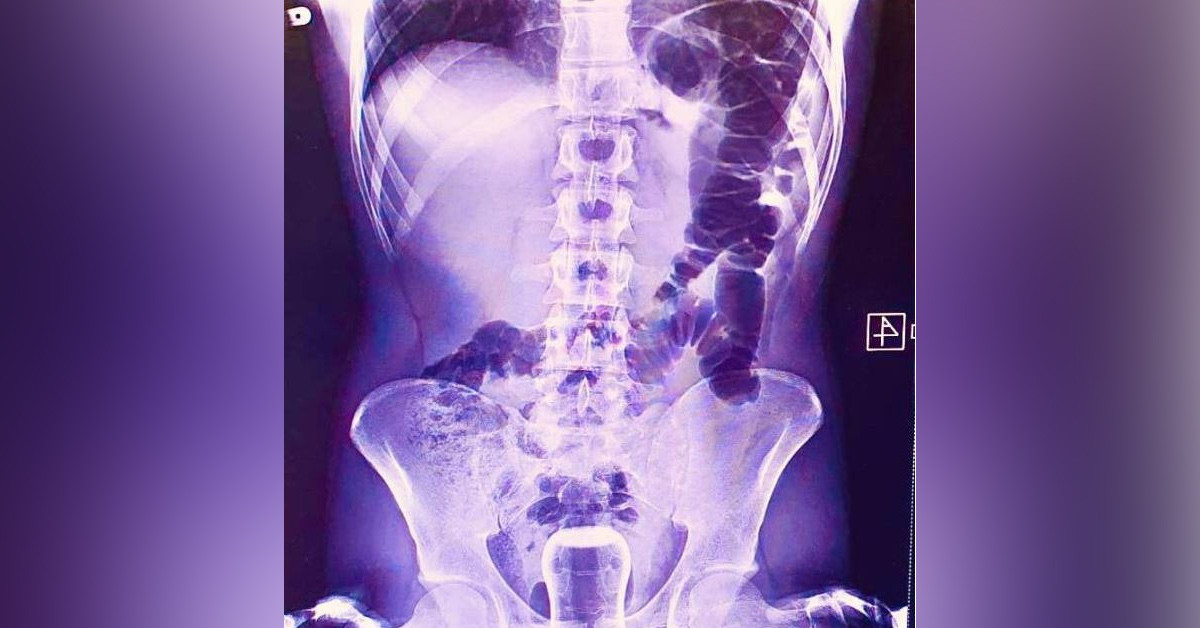

Midem çöplük gibi derken ciddi olanlar varmış...